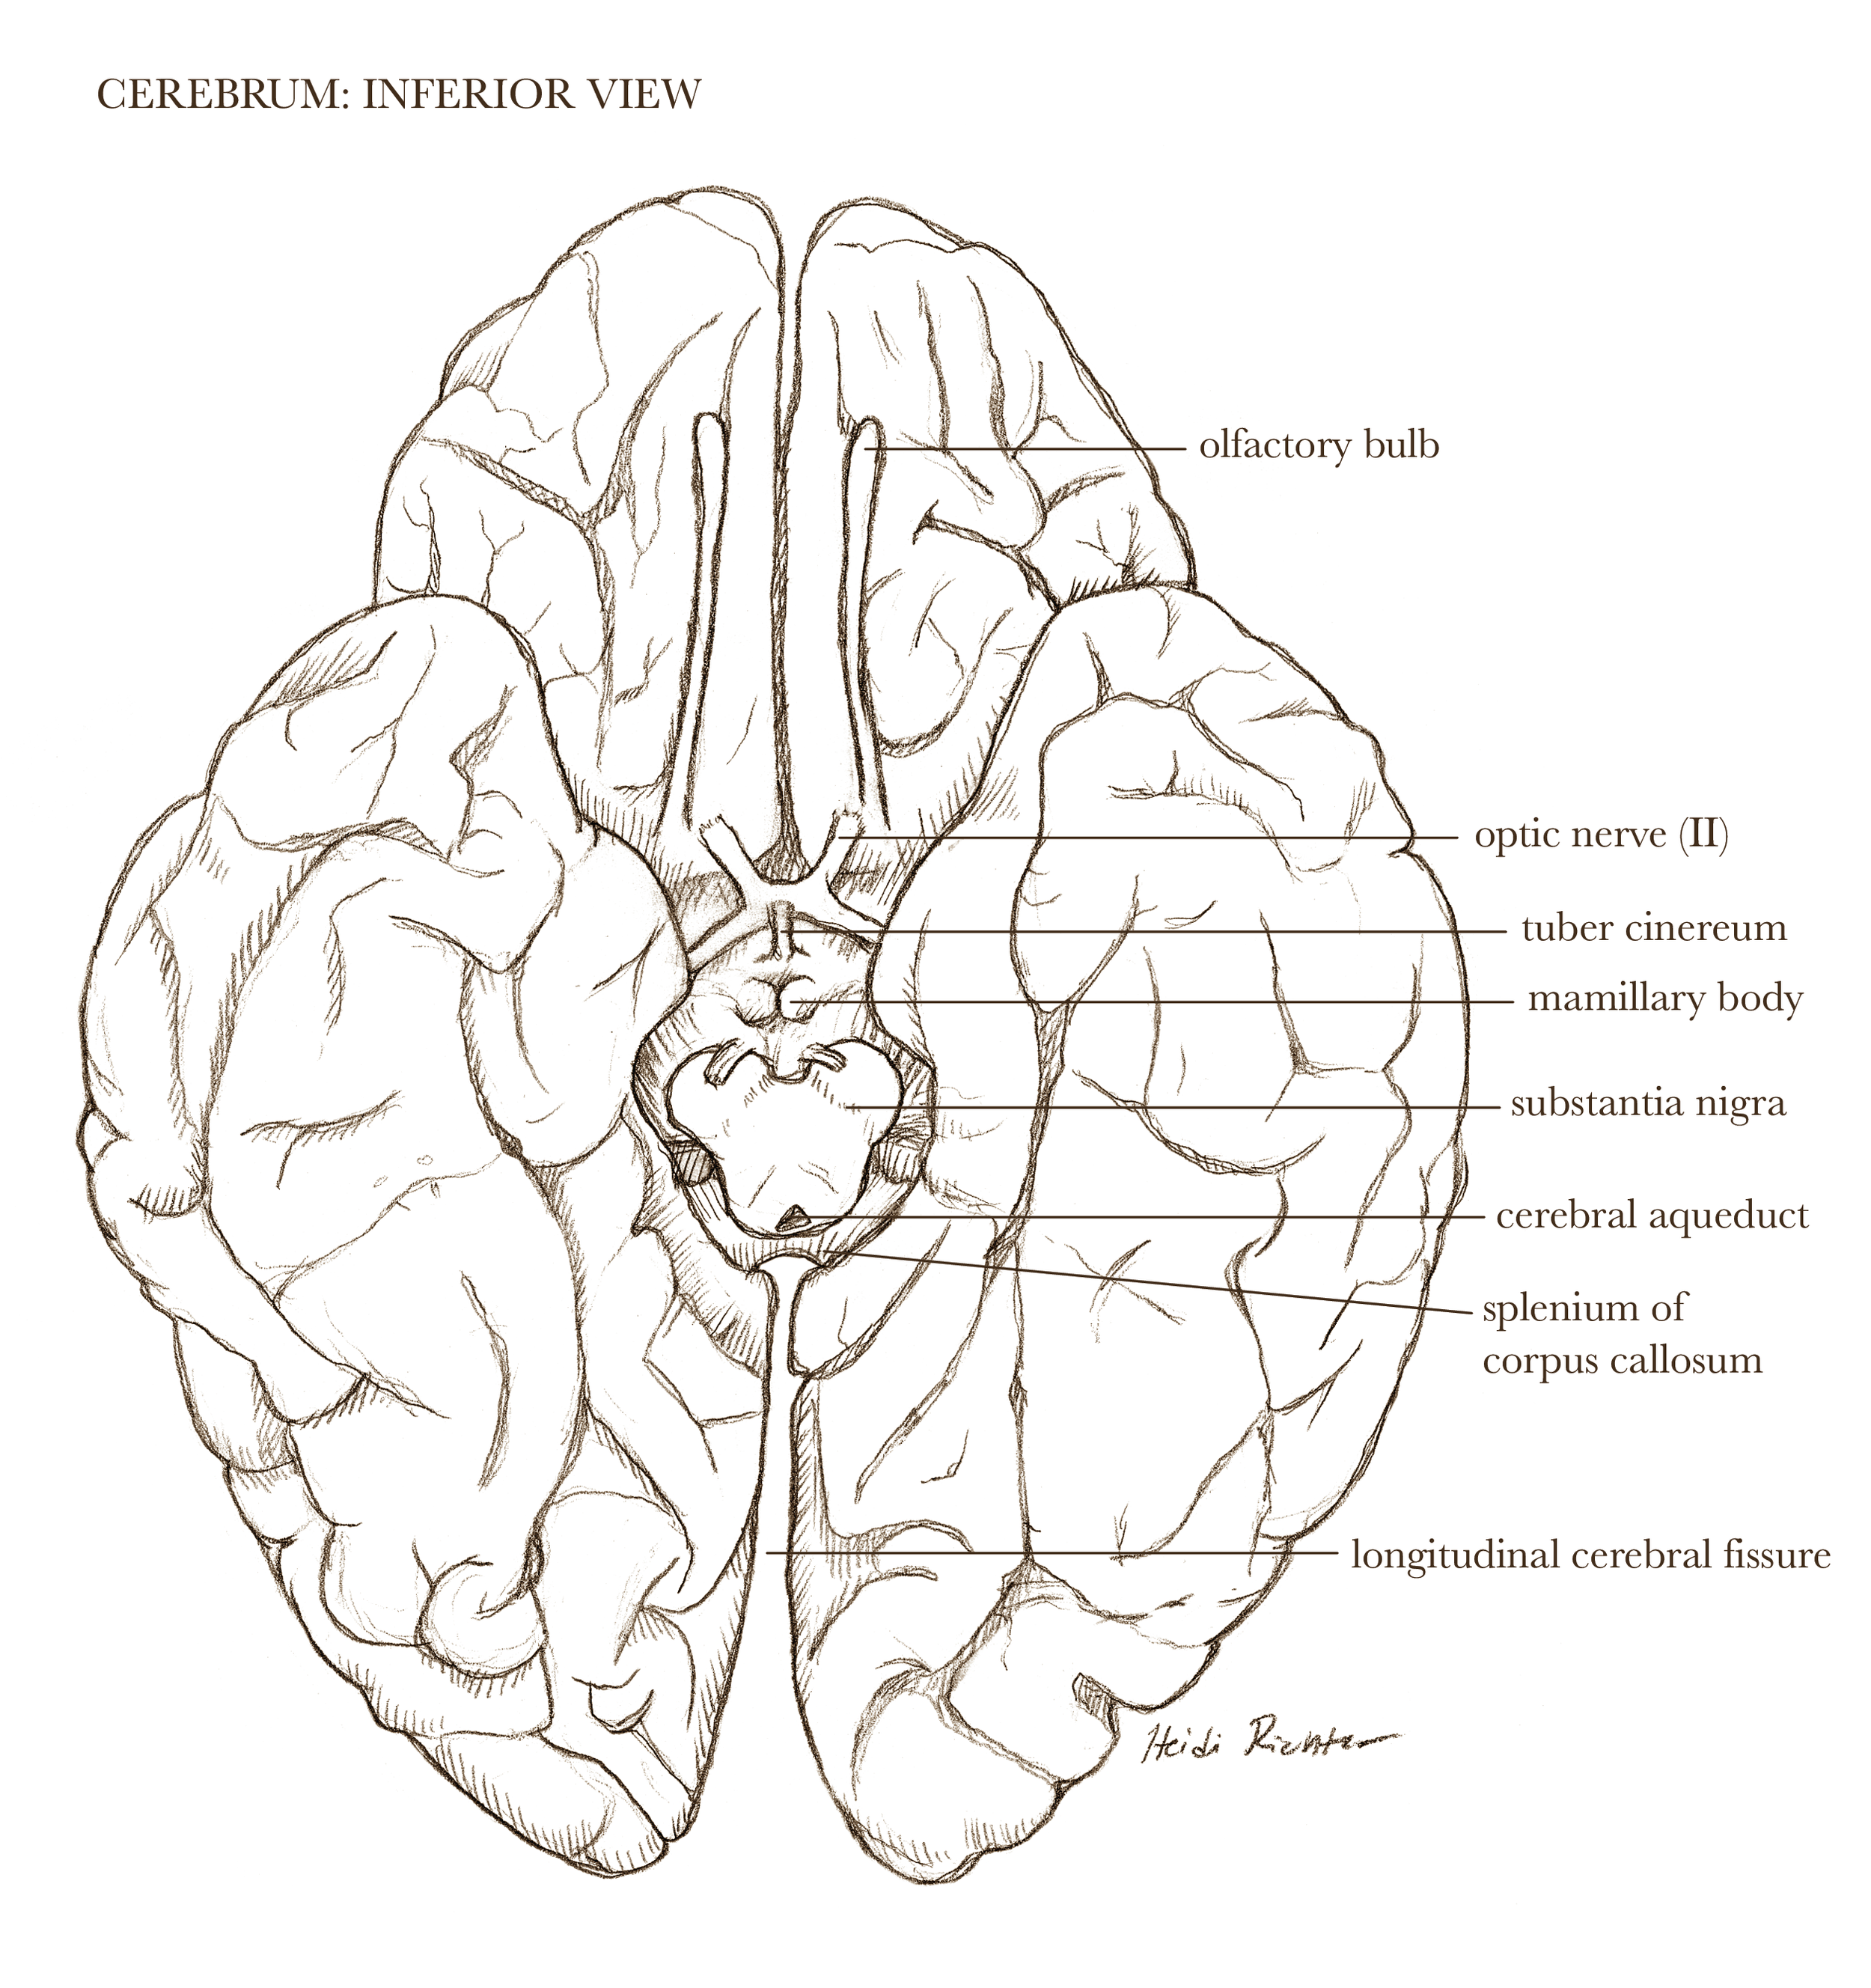

Textbook illustration

I have nearly twenty years of experience in text book publishing, having illustrated books from grade school to graduate level, and in subject areas from human anatomy to biology and geology. I never say no to projects involving dinosaurs.

Medical-legal illustration

I can create client-specific illustrations for your personal injury or malpractice cases to both inform the jury (who often don’t have experience with hospital images) as well as gain sympathy for the affected individual. I can work directly with medical experts to ensure accuracy and admissibility in court.

Patient education

Illustrations can help patients understand surgical procedures they or a loved one are planning to have, or explain how a medication works in the body.

Grants and journals

An illustration in your journal article or grant, customized to your research, can emphasize your findings and intents of your future studies. It could be more affordable than you think!

Licensable work

Illustrations shown below are owned by the artist and available for non-exclusive licenses, contact me for more information.